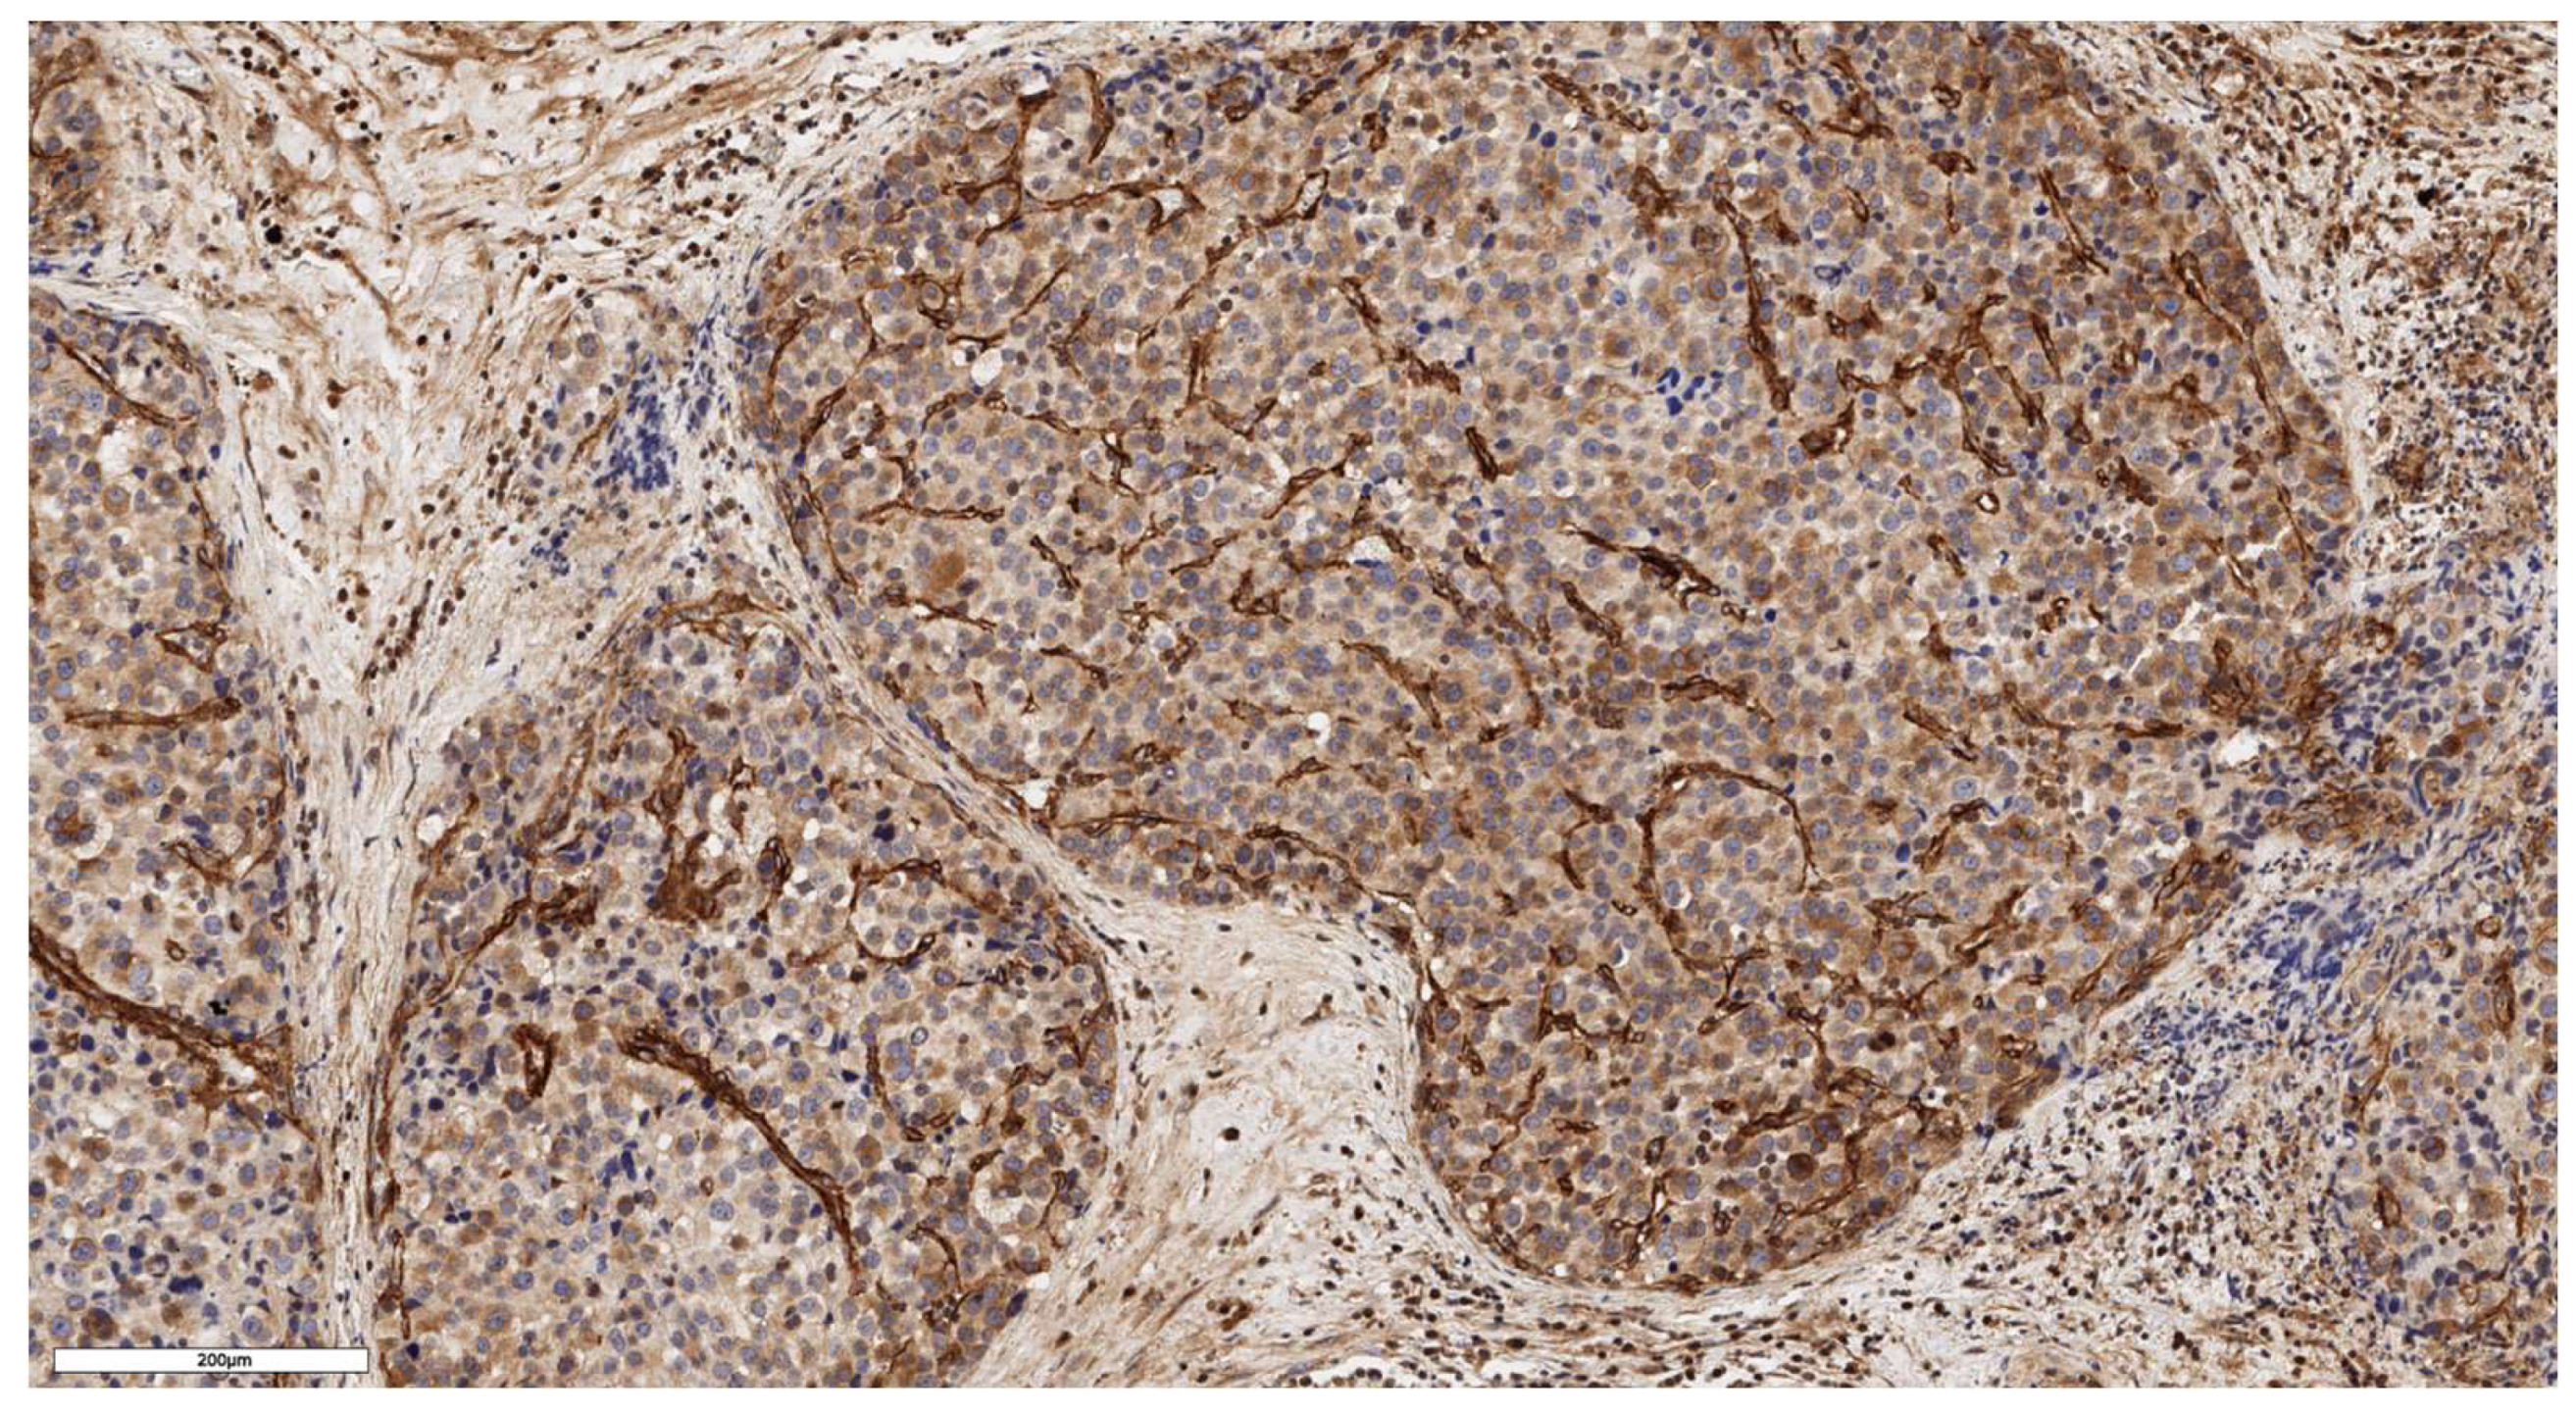

An analysis of the association between CD90 expression and the clinicopathological data of patients was conducted (Table 2). The number of CD90+ cells in the tumor parenchyma was relatively higher in samples of conventional and mixed histological subtypes compared to other histological subtypes of ACC (Figure 2, Figure 3, Figure 4 and Figure 5); however, these differences did not reach statistical significance (p = 0.161). No significant differences in CD90 expression beneath the tumor capsule were found across histological subtypes either.

Figure 4. Mixed subtype of ACC. The parenchyma of the tumor. IHC reaction with CD90 marker, x150.